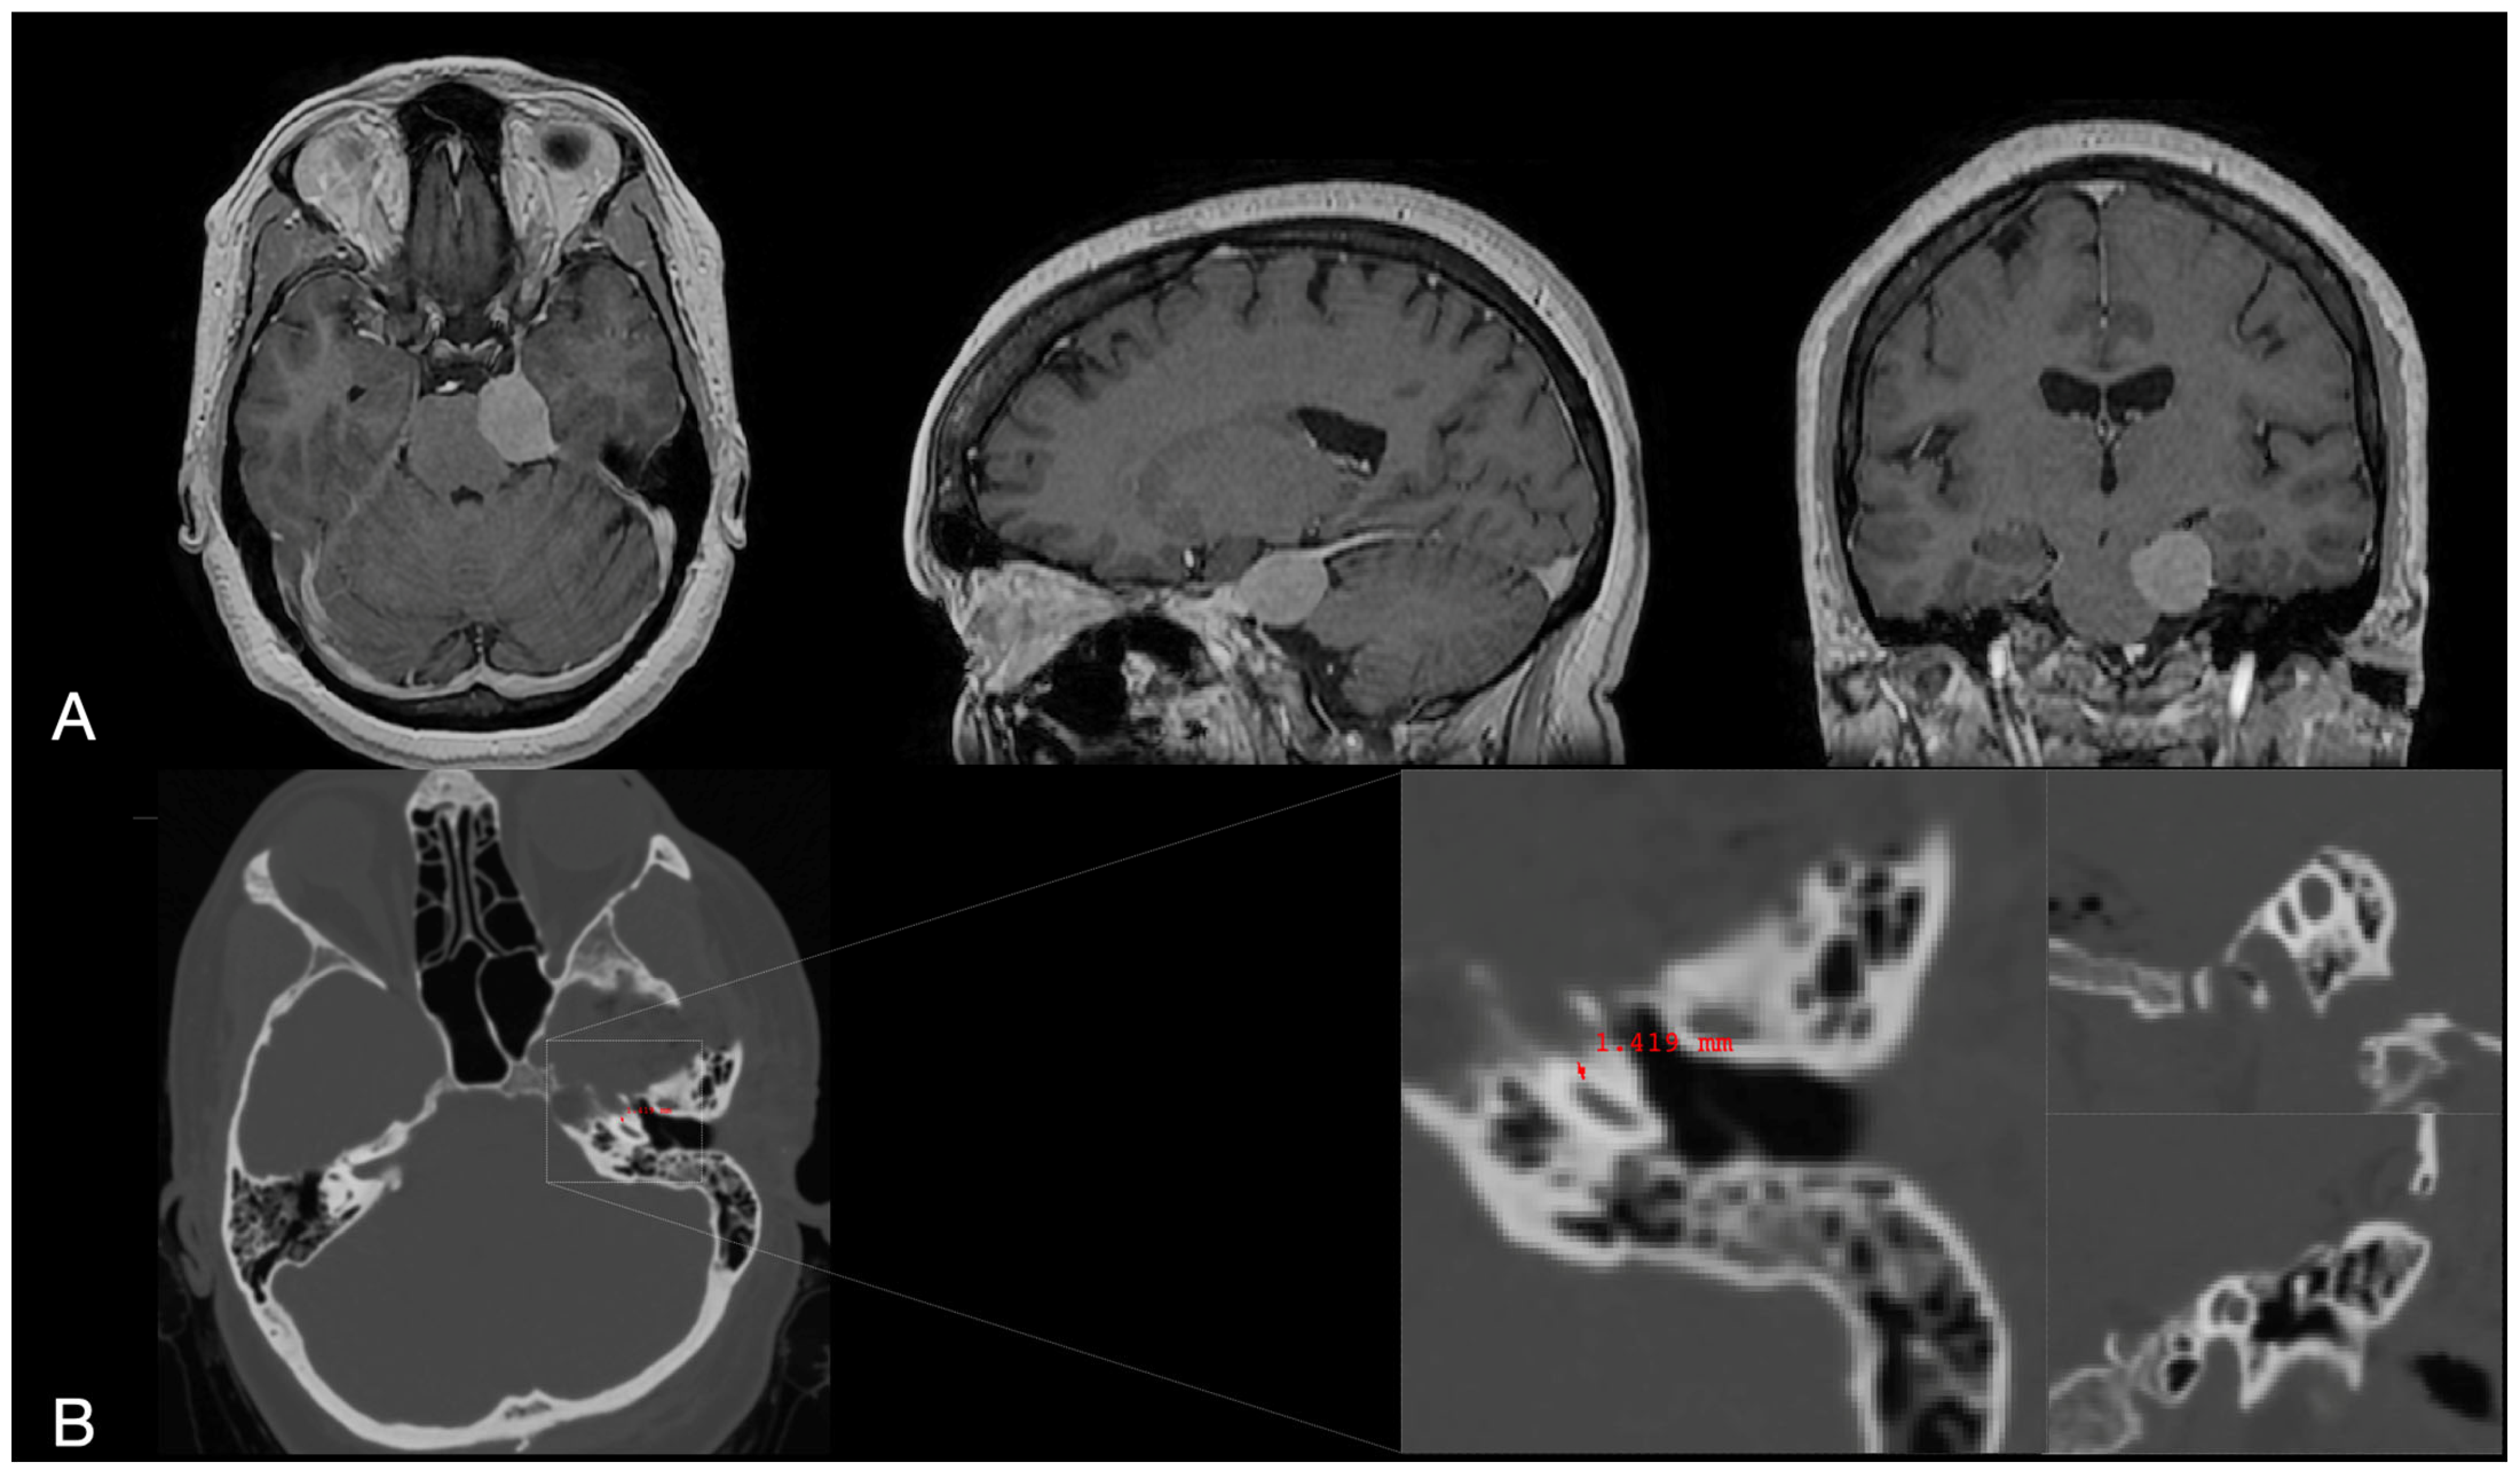

2.2. Clinical Case

3.2. Surgical Application